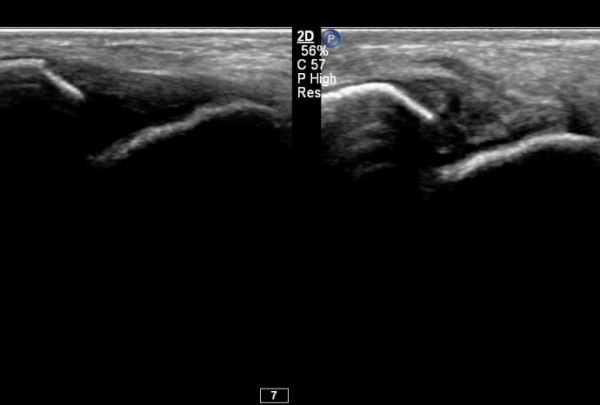

°ÇÃø °Å°ñºñ°ñÀδë Á¾´Ü¸é°Ë»ç¿¡¼­ Á¤»óÀûÀÎ ¼Ò°ßÀ» º¸À̰í(»çÁø 6),

°ÇÃø°ú ºñ±³Çϸé È¯ÃøÀÇ º´Àû ¼Ò°ßÀÌ ¶Ñ·ÈÇÏ´Ù(»çÁø 7).

ÃÊÀ½ÆÄÅõ½ÃÇÏ ºÎÇϰ˻翡¼­ ºñ°ñ°ú °Å°ñÀÇ ºñÁ¤»óÀûÀÎ ¹ú¾îÁüÀÌ °üÂûµÈ´Ù(÷ºÎ µ¿¿µ»ó 1).

ÃÊÀ½ÆÄÅõ½ÃÇÏ ºÎÇϰ˻翡¼­ ºñ°ñ°ú °Å°ñÀÇ ¹ú¾îÁüÀÌ Å©°Ô °¨¼ÒµÇ¾ú´Ù(÷ºÎ µ¿¿µ»ó 2).

ÃÊÀ½ÆÄÅõ½ÃÇÏ ºÎÇϰ˻翡¼­ ºñ°ñ°ú °Å°ñÀÇ ¹ú¾îÁüÀÌ º¸ÀÌÁö ¾Ê¾Æ ÀδëÀÇ ¾ÈÁ¤¼ºÀÌ È®º¸ µÇ¾úÀ½ º¸¿©ÁØ´Ù(µ¿¿µ»ó 3).